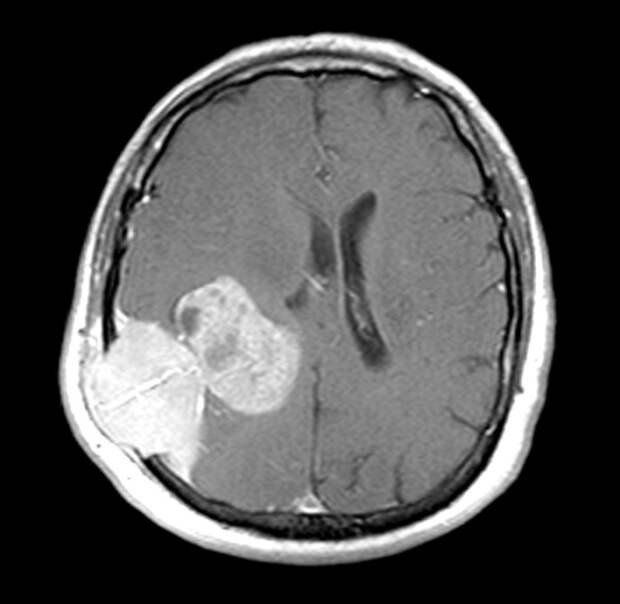

12. Опухоль головного мозга